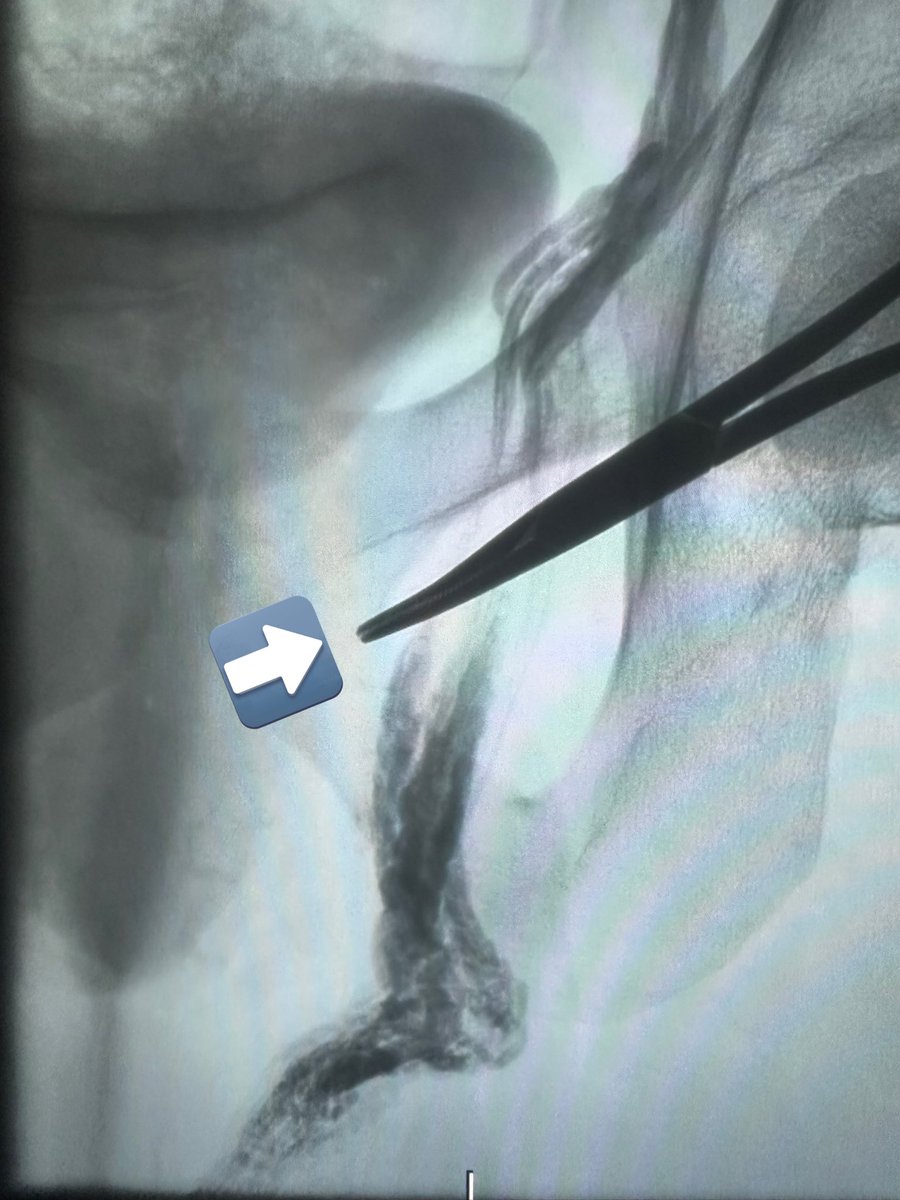

Case 133: with Bhavesh Popat Antariksh V. Vijan . Seeing good on-table wound vascularity post plasty . CLI; ulcer on heel; post debridement showing ischemic edges; angio showing PTA long seg CTO with distal ATA CTO; antegrade crossing with support Cath-Progreat-Fielder 0.14 . Post